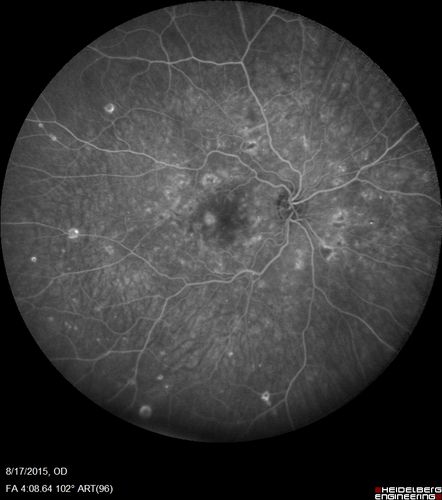

West Nile Virus Multifocal Choroiditis and diabetic retinopathy

Multifocal and clustered focal lesions are from west nile virus. The retinopathy is probably diabetic but could also be related to west nile virus